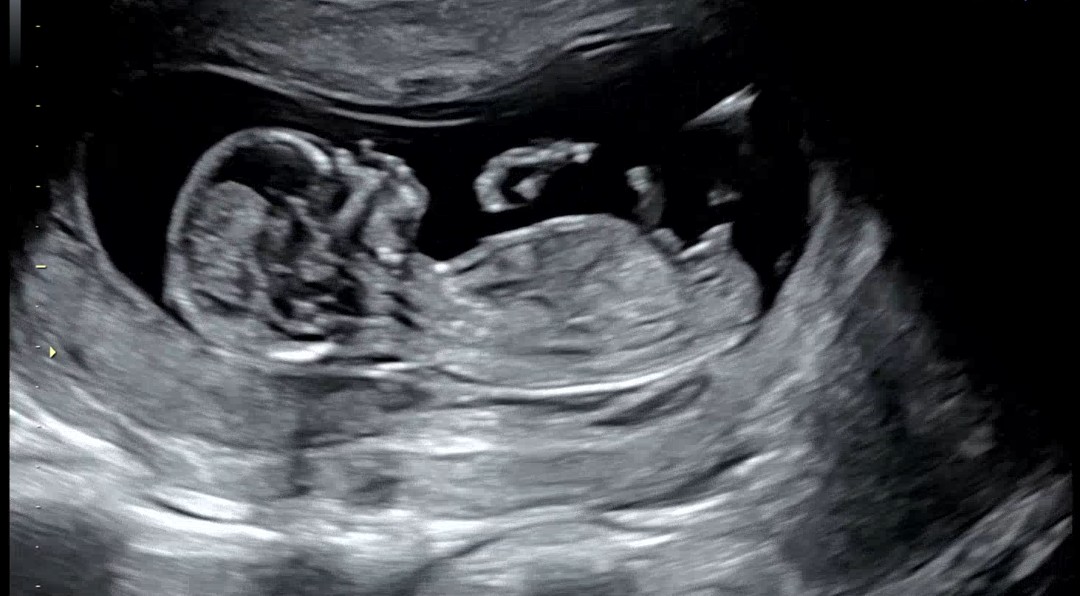

성별 궁금해요 13주차 0일

아들일까요 딸일까요^^ 생식기결절과 척추각이라고 하는게 어디선인지 모르겠어요ㅠㅠㅎ 마구마구 참견 부탁드려요 ^^